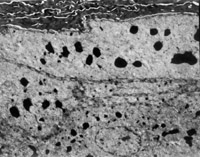

經(jīng)MEBT/MEBO治療20天,電鏡觀察到基底細(xì)胞層與纖維母細(xì)胞之間的半橋粒連接,同時可見纖維母細(xì)胞內(nèi)粗面內(nèi)質(zhì)網(wǎng)結(jié)構(gòu)和線粒體增生活躍(圖5-3-19~5-3-21)。 MEBT/MEBO治療30天后,上皮組織再生修復(fù),已基本完成,創(chuàng)面組織切片顯示膠原纖維成熟,排列整齊(圖5-3-22),直徑為0.1~0.5祄,并可見明暗相間周期性橫紋(64nm),未見到膠原纖維扭曲和呈旋渦、菜花等病理形態(tài)。

5-3-22 MEBT/MEBO治療30天,整齊排列的膠原纖維,纖維均勻一致直 徑 0.1~0.5祄,有明暗相間的周期性橫紋(64nm)